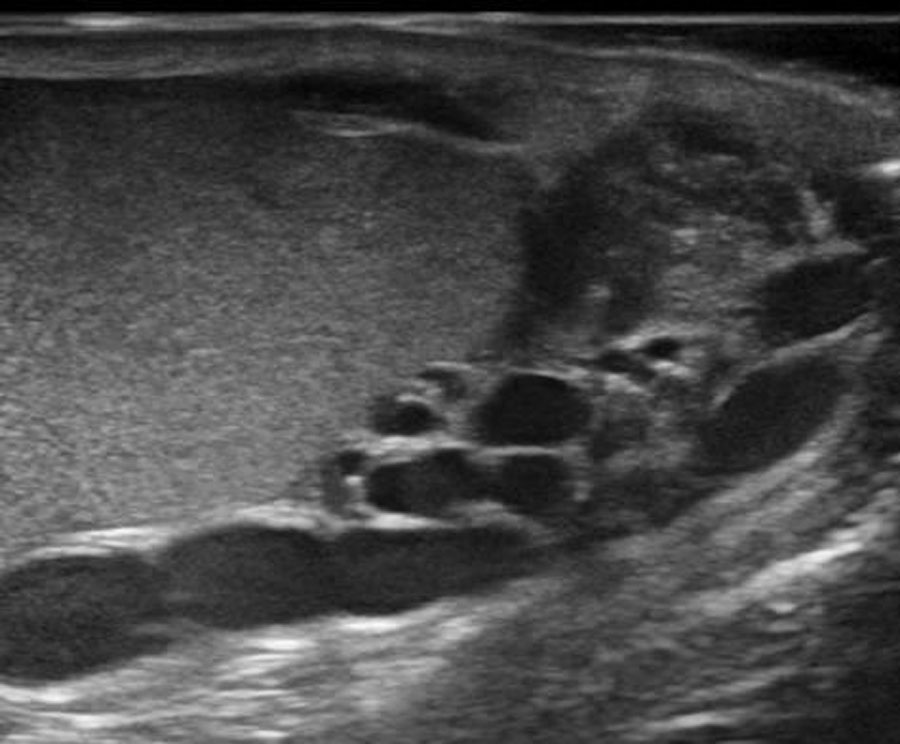

Při vstupním vyšetření je provedeno podrobné fyzikální a sonografické vyšetření šourku za použití Dopplerovy metody, rozbor kvality ejakulátu a odběr krve ke stanovení hladiny mužských hormonů. Dle získaných výsledků se stanoví stupeň varikokély a pravděpodobnost, že z chirurgického odstranění varikokély bude pacient profitovat.